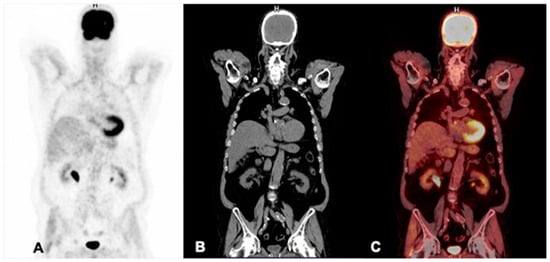

6. Diagnosis with PSMA PET/CT

6.4. Assessment of Response to Treatment